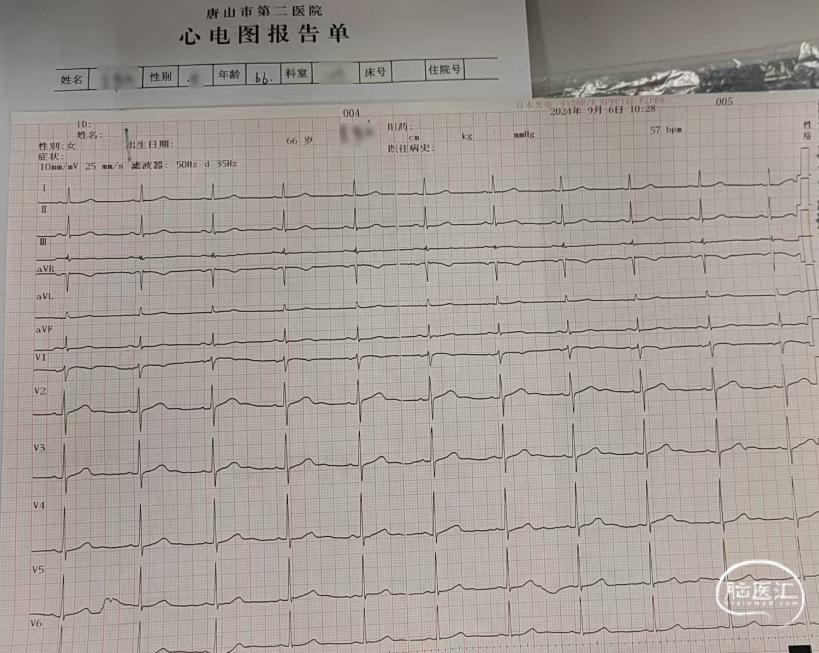

心脏彩超及甲状腺彩超。